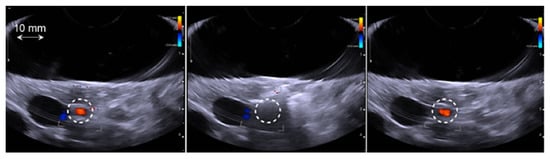

Figure 3.

Typical example in group 4 of a temporary spasm. From left to right: Color Doppler imaging of the targeted artery (white circle) just before the HIFU treatment, just after the HIFU sonication and 12 min after the sonication. Normal blood flow was recovered on average 12 min after the temporary spasm in all cases.

Systematic temporary arterial spasm was observed in groups 3 and 4, which were treated with acoustic energies of 45 kJ and 52 kJ, respectively (corresponding to emitted acoustic powers of 124 W and 143 W, respectively). In these two groups, all spasms occurred during the first sonication. On average, arterial spasm was observed 51 ± 18 s (min: 29 s–max: 71 s) before the end of sonication. Normal blood flow reappeared in the treated artery at an average of 12.6 ± 6.2 min (min: 7 min–max: 22 min) after treatment. Interestingly, it was possible to perform two additional sonication procedures without additional arterial spasm in all cases.

The exposure time was constant for all sonication procedures (900 s with a duty cycle of 40% HIFU exposure and 60% Doppler color imaging). The effect of the emitted energy (acoustic power) on the targeted artery was clearly observed (Table 2). No arterial spasms were observed for treatments performed using an emitted acoustic energy of 30 kJ (corresponding to an emitted acoustic power of 83 W), even when the treatment was repeated three times. In this group, Doppler color imaging showed normal blood flow after sonication in all cases. In group 2, which was treated using an emitted acoustic energy of 40 kJ (corresponding to an emitted acoustic power of 110 W), temporary arterial spasm was observed on Doppler imaging in two animals during the third sonication. No blood flow was observed in the treated artery immediately after sonication in these two cases. Normal blood flow was observed on Doppler imaging 12 min after the treatment (Figure 3).